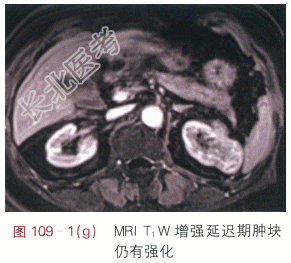

影像学资料如图109-1(a~g)所示。

读片分析:图109-1(a)示CT平扫时左肾中部见一肿块,大小约3.4cm×2.9cm,致左肾局部隆起,肿块密度均匀,CT值约为19.9Hu;图109-1(b)示增强后动脉期肿块明显强化,强化不均匀,平均CT值约为141.0Hu;图109-1(c)示增强后静脉期肿块强化减弱,平均CT值约为104.1Hu。图109-1(d~g)为同一患者MRI图像,图109-1(d)示T₁WI平扫肿块呈等低信号,图109-1(e)示T₂WI肿块呈等高信号灶,信号不均匀,肿块边界清晰,边缘有包膜,图109-1(f)示增强后T₁WI动脉期肿块明显强化,强化不均匀,图109-1(g)示增强后静脉期肿块强化减弱,呈相对稍低信号灶。患者诊断为左肾透明细胞癌。